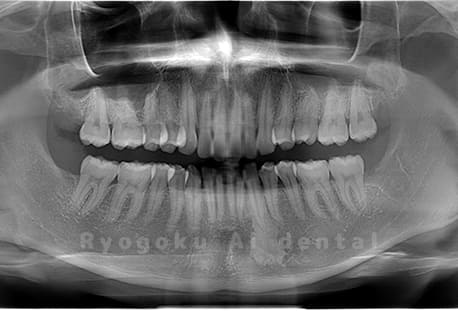

Case03

-

- 原因

- 上顎、下顎の親知らず

- 治療内容

- 上下4本の親知らずを抜歯したケースです。

<リスク・副作用>

手術後は痛み、腫れ、痺れなどの副作用が生じる場合があります。